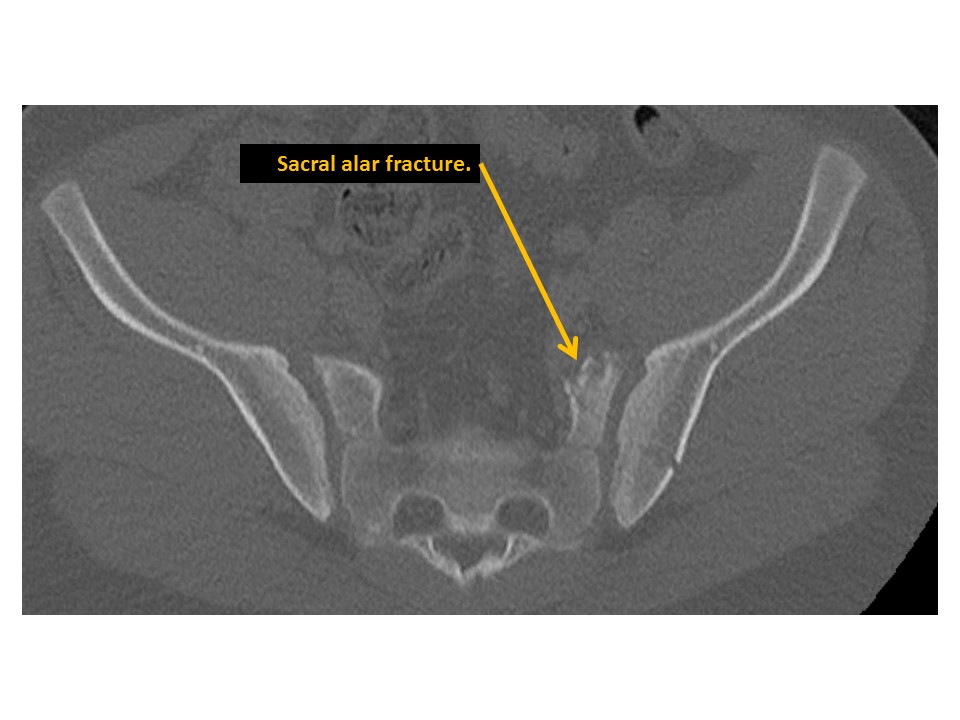

SACRUM and SACROILIAC JOINTS

A fracture is present. [Yes/No]